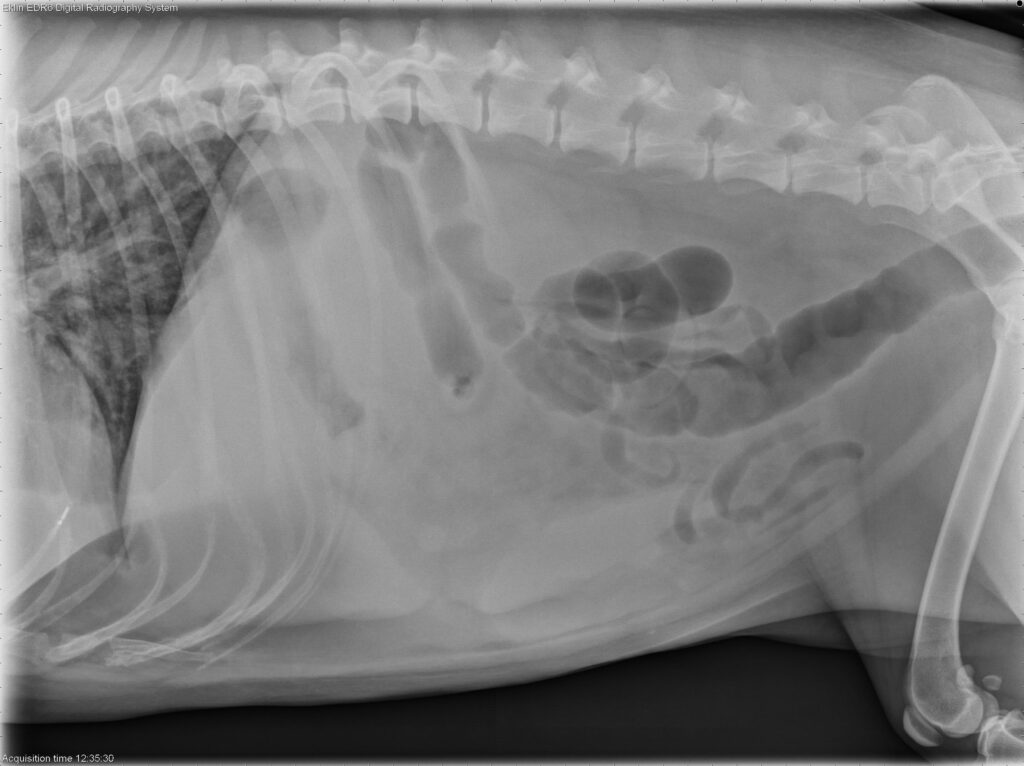

Radiology Quiz September 2025

History 10 year old male castrated dog. History of chronic hematochezia for the last 3 months.

...